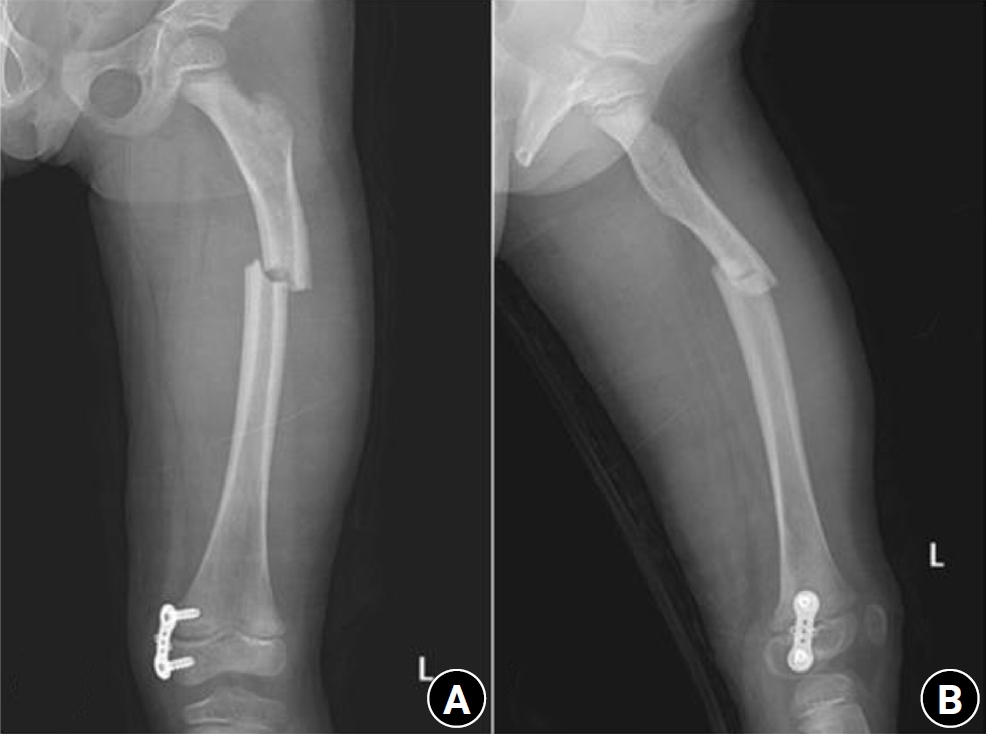

Fig. 5.

Radiographs of the same patient with a proximal one-third fracture of the left femur. (A) Anteroposterior view. (B) Lateral view.

jmt-2025-00388f5.jpg

An 8-year-old female patient visited our emergency room complaining of pain in the left thigh that began on the day of her visit. She slipped and directly injured her thigh upon falling to the left. Initial examination revealed normal laboratory findings, including serum calcium levels of 9.0 mg/dL and inorganic phosphorus levels of 4.7 mg/dL. Radiographic evaluations, including anteroposterior and lateral views of the left femur, demonstrated a transverse irregular fracture line in the proximal one-third area of the left femur, accompanied by lateral cortex hypertrophy. Importantly, the possibility of malignancy or infection as contributing factors to the fracture was considered low. Two years prior, the patient had visited the pediatric department of our hospital due to concerns about her height, which was below that of her peers. Following genetic testing, she was diagnosed with osteogenesis imperfecta and has since been monitored by both the pediatrics and orthopedics departments. At that time, lateral bowing of both femurs was observed in both lower extremities during standing anteroposterior evaluations (Figs. 4, 5). She had previously undergone epiphysiodesis on both femurs due to genu valgum. After diagnosis, the patient underwent open reduction and internal fixation using an ender nail. Follow-up evaluations indicated successful bone union at the fracture site.